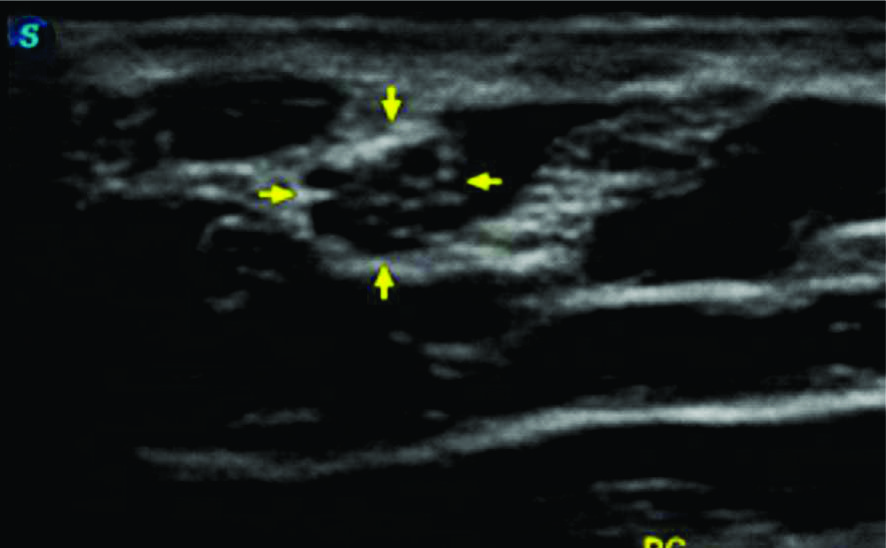

Figura 11

Inestabilidad del nervio cubital

A- Corte transversal comparativo en el túnel epitrocleo-olecraneano con el codo en extensión: se observa el nervio cubital (flechas amarillas) a izquierda se encuentra engrosado e hipoecogénico con pérdida del patrón fascícular habitual lo cual es compatible con signos de neuropatía. B-Corte transversal comparativo en el túnel epitrocleo-olecraneano con el codo en flexión: se observa como el nervio cubital (flechas amarillas) a izquierda tiende a subluxarse, mientras que a derecha tiene una situación normal. C-Corte longitudinal sobre el nervio cubital (flechas amarillas) izquierdo, se demuestra la transición entre el patrón nervioso normal en brazo (recuadro color azul) y el patrón nervioso neuropático en codo (recuadro color rojo). EM- Epitroclea medial, Flecha roja- Canal epitrocleo olecraneano, Asterisco- músculo tríceps.